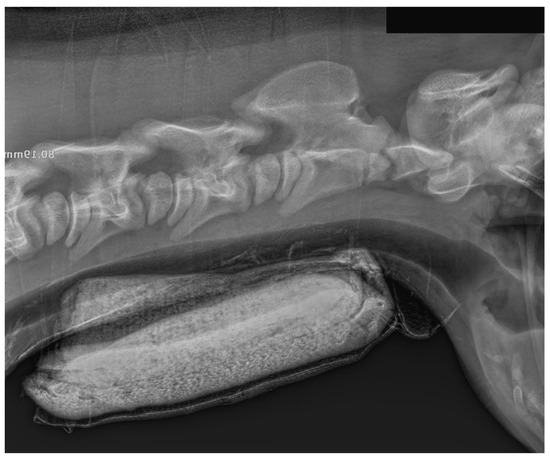

Case Presentation